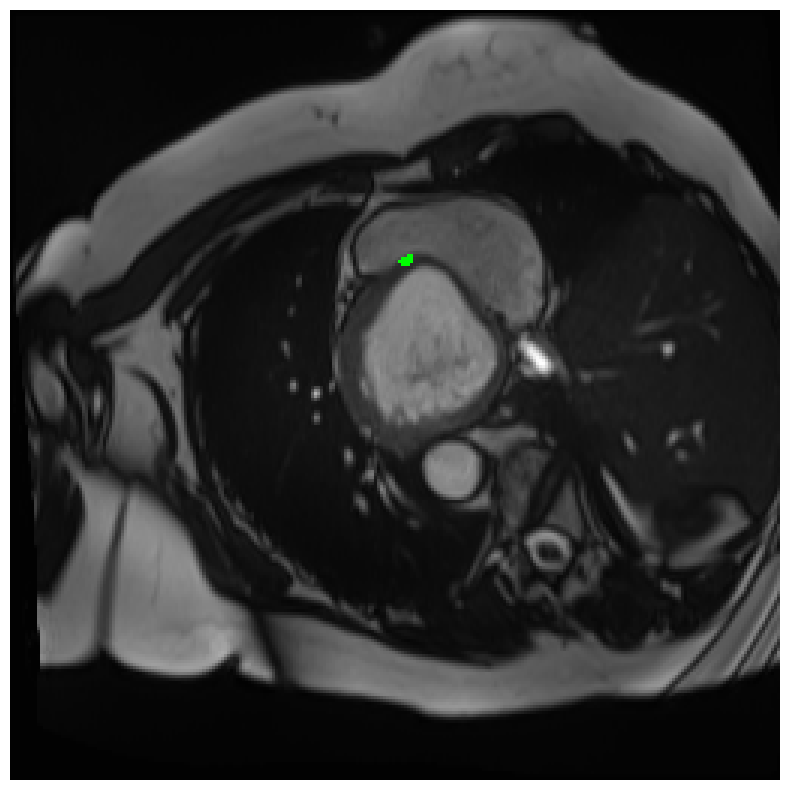

Generally, given an exact, full annotation of an object, such a Euclidean signed distance map encodes also information on the shape of an object. But when using a weak ground truth , where and , inferring a correct extent and shape of the objects is nontrivial. As shown in 1(b), Euclidean distance calculated from a point label source grows radially, regardless of the actual shape of the object, and thus makes little sense from an information point of view. Under the assumption of intra-object homogeneity and inter-object contrast (w.r.t intensities), this problem can be circumvented to a degree by using a distance function that takes also intensity values into account. An example of a commonly used distance measure with an intensity component is the Geodesic distance ([34]). Let denote a path between , with and being neighbors under a chosen adjacency relation. Reusing the notation from before, a Geodesic distance map from the boundary of the ground truth class , , can be defined as

Both the Intensity and the Minimum barrier distance are defined exclusively on the image intensity space. However, from the examples of distance map in 1(d), we can notice that the values still increase somewhat radially from the annotation. This behaviour is similar to the one of the Geodesic distance in 1(c) (which actually includes the spatial proximity in its definition), and is due to the summing operator in the general Geodesic distance definition in Equation 3. While the intensities of two neighboring pixels on a path may be the same, that will rarely be the case in real life, noise riddled images. This makes the Intensity distance function approximately monotonically increasing with increasing length of the path (in space), even on paths where the intensity is mildly fluctuating (e.g. consider a path with even pixels intensity value of and odd pixels intensity value of ). One could thus argue that such a definition of a distance, despite being based exclusively on intensities, is still capable of loosely encoding the spatial distance information.

On the other hand, while we can see that the MBD based maps are similar to Geodesic and Intensity ones (1(e)) with respect to the object shape recovery, they have a less pronounced and smooth increase in the values outward from the source point.

In contrast to Euclidean distance, the Geodesic, Intensity and Minimum barrier distance maps all encode contrast sensitivity and preserve the object structures by harnessing the intensity information of the underlying image. This holds even when calculated from point sources. In practice, using such maps for network training could mean a lower penalty for false positives that occur farther from the point annotation but are close to it in intensity. Thus still enabling the propagation of a sort of shape information (as it can be inferred from the raw image intensities).

We normalize the volumes and resize the slices to pixels. As the official dataset comes with full annotations, we create a synthetic point ground truth. This is done by first randomly choosing the centers of the point annotations within the class masks, followed by filling an ellipse with axes lengths of and (in pixels) around each center. The intersections of these elliptic discs with the underlying full annotations are then used as our point ground truth. See Figure 2 for an example of the created weak annotation mask. The point annotations are created for every slice, one for each foreground object present in the slice.